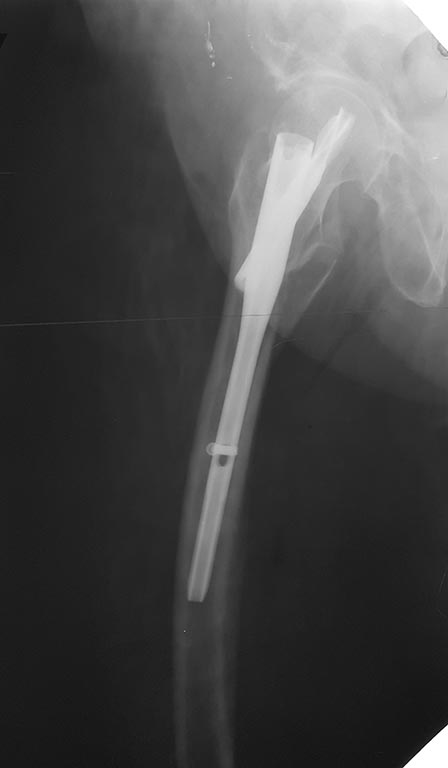

[Ortho] БИОС PFNA варусного бедра

Еще одна проекция